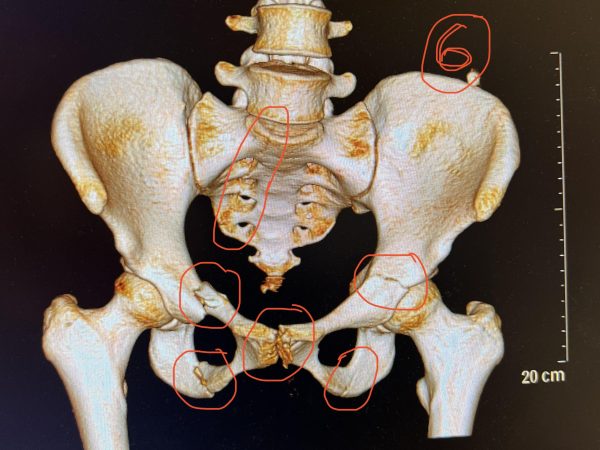

The impact of flat landing left Grace severely concussed and internally bleeding. When they airlifted her to the Royal North Shore Hospital, a full body CT scan revealed six unstable fractures in her pelvis. After a night in ICU, she had an emergency surgery the following morning to stabilise the pelvis and broken sacrum with three screws.

After two weeks of this, one of Grace’s fractures had moved, and she needed a second surgery, leaving her with another four screws and a plate.

“I was airlifted from the accident to Royal North Shore hospital. That night, I was put in ICU, and the next morning, I had my first surgery. Two weeks later I had to have a second unexpected surgery. I stayed in the hospital for a total of 31 nights. Those two surgeries left me with seven screws and a plate. I came home, still non-weight bearing for four weeks. There’s a staircase at the front of our house, so I was lifted in by the paramedics and then confined to my room and the kitchen, it started to feel a little claustrophobic by the end…